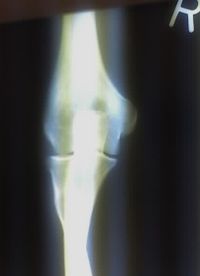

Projectional radiography of the knee in a modern X-ray machine. | |

التصوير الشعاعي إنگليزية: Radiography: وهو يستخدم الأشعة السينية لرؤية الأجزاء غير المرئية أو صعبة التصوير. الهدف الأساسي من الأشعة السينية المستخدمة في التشخيص هو تصوير داخل الجسم، وبشكل خاص العظام والتي يمكن رؤيتها بدقة مثلى (128 تدرج للون الرمادي).